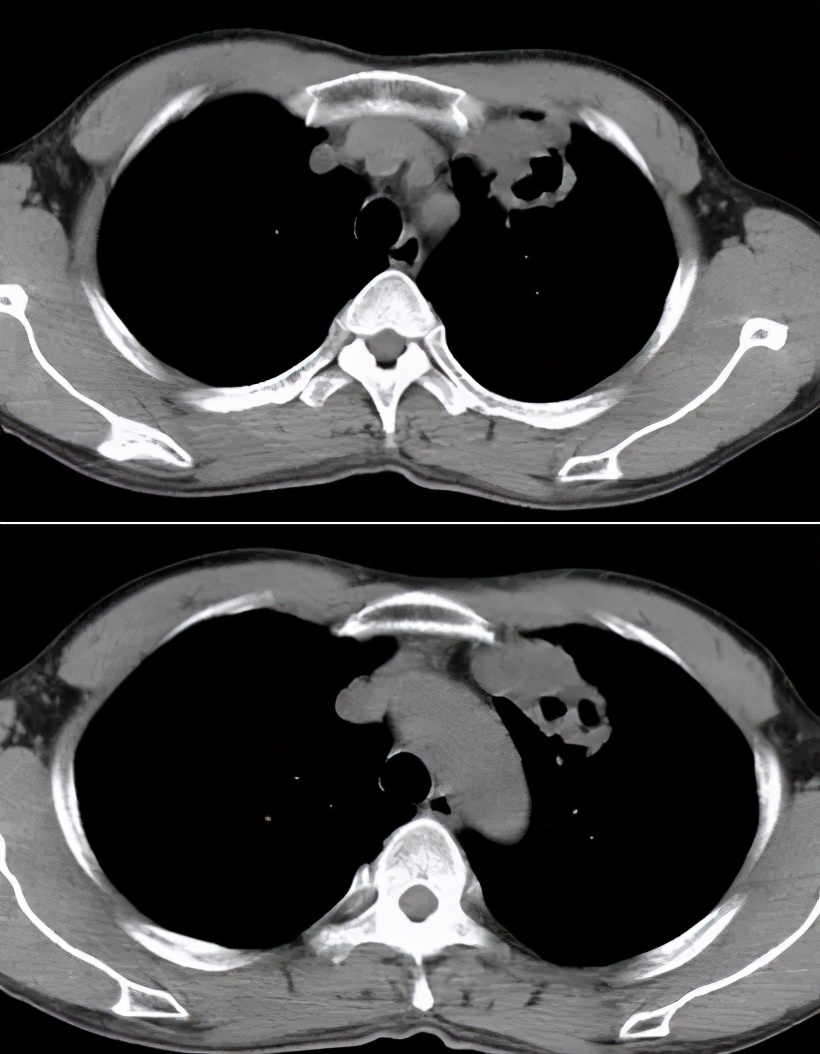

针对ICH的肺结核病影像表现,我与大家分享一些病例

病例1:

68岁,男性,2017年1月入院。主诉:反复发热2月,右侧胸隐痛;现病史:胸部CT示双肺散在炎症,抗感染治疗(头孢菌素、呼吸喹诺酮)后有吸收;但症状反复。

寻常型天疱疮,长期美卓乐、硫唑嘌呤治疗;类固醇性糖尿病。

CRP 196↑ mg/L;白细胞计数 9.12 ×10^9/L 中性粒细胞% 98.2;反复痰找抗酸杆菌(-)。

右侧胸腔穿刺,抽得脓性胸水,胸水涂片见抗酸杆菌4+。

图:2017-1 胸部CT:左肺上叶后段团片影,较前片有所减小;两肺多发炎症,较前片部分吸收;右侧胸膜增厚、胸腔积液,较前片有所增多。

病例2:

男性,42岁。 2008年诊断干燥综合症,当时胸部影像学未见异常。糖皮质激素30毫克/日 ,减量过程中口干症状加重,2009年7月再次全身检查,胸部CT见左上肺尖段软组织影,伴空腔。(似乎存在空洞,有些低密度区,但究竟是不是空洞呢?需要进一步确认。)

病灶穿刺病理:肉芽肿性炎伴坏死,抗酸染色+。

抗痨治疗6月后:

病例3 :

男,50岁,发热1月;骨穿:感染象;胸部CT:右肺阴影,纵膈淋巴结肿大。

这位患者入院时,完全像是白血病化疗过程中出现的改变,那么,会不会是白血病的肺部浸润呢?但是白血病肺部浸润较多见间质的浸润,而这位患者病变呈片状,是实质性的浸润……我们给患者做了骨穿,证实是感染象。

最终痰抗酸染色阳性、血HIV阳性;患者为同性恋。

病例4:

男性,26岁。2015年8月入院,因「咳嗽、咳痰一个半月,胸痛半月,加重伴高热一天」入院。 糖尿病病史8年余,平素血糖控制差,入院时尿酮体+++。

图:胸部CT:右侧液气胸,右肺实变,伴空洞及气液平。

病例5:

男,52岁,溶血性贫血,激素治疗43天。

最初完全按照大叶型肺炎、细菌性肺炎治疗,没有明显效果。最后出现播散,用了机械通气,出现气胸等等。

病例6:

这位患者是急性单核细胞性白血病,化疗2个疗程后出现病症——发热、咳嗽,咳黄痰,很多人会因此想到细菌性肺炎。但事实上,做了气管镜、采样、活检,证实有大量的抗酸杆菌。肺组织活检证实是肉芽肿改变,最后确诊肺结核。

经过治疗以后明显吸收好转:

病例7:

患者是混合性结缔组织疾病,激素治疗6个月后出现发热,肺部病灶明显增多,两侧情况不一样,我们冒了很大风险给他做支气管肺泡灌洗,做刷检、做活检,刷检时也找到了抗酸杆菌,但活检的结果是:既有一般的结缔组织的肉芽肿性改变,同时也看到有结核的干酪样坏死。因为患者是在激素减量过程中出现的症状,所以我们考虑是既有结缔组织疾病,又合并了肺结核。